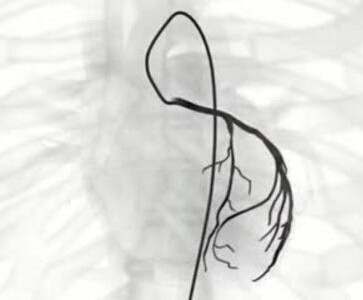

冠脉造影检查。能进一步明确血管阻塞情况。它是评估心脏病严重程度以及判断是否行支架或搭桥治疗的最好方法。